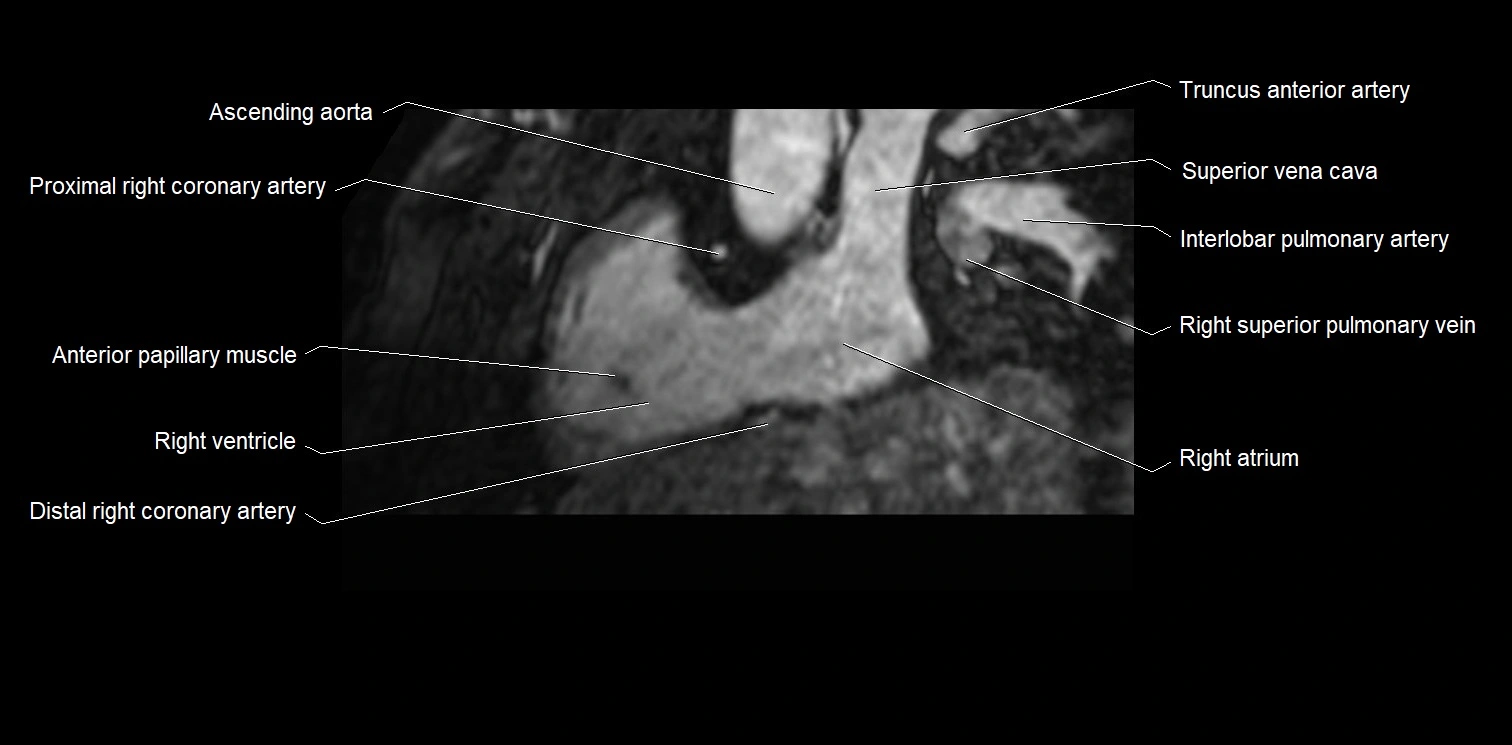

MRI image